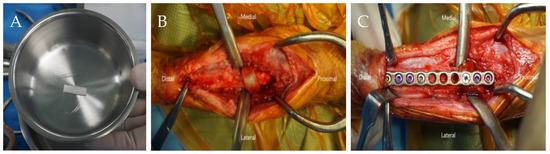

The first surgical treatment was performed one week after referral (Figure 2A–C). The patient was premedicated with 0.2 mg/kg of intravenous (IV) midazolam (midazolam, Inj®; Bukwang Pharm, Seoul, Republic of Korea). Anesthesia was induced with 6 mg/kg of IV propofol (Anepol, Inj®; Hana Pharm, Seoul, Republic of Korea) and maintained with inhaled isoflurane (Ifran; Hana Pharm, Seoul, Republic of Korea) in oxygen. Cefazolin (Cefazolin, Inj®; Chong Kun Dang Pharm, Seoul, Republic of Korea) a prophylactic antimicrobial agent, was administered before surgery and intraoperatively at an initial dose of 25 mg/kg IV, with repeat doses every 90 min throughout the procedure. The dog was positioned in lateral recumbency, with the affected limb placed in the uppermost position. The skin was aseptically prepared for surgery. After palpating the olecranon, a craniomedial skin incision was made at the proximal radius. Proximal radial defects were observed, and a predesigned hybrid ESF (IMEX™ Veterinary, Inc., Longview, TX, USA) was applied, combining type II linear ESF at the proximal site of the fracture and two circular ESFs at the distal site of the fracture. The linear ESF was equipped with six connecting clamps and fixation pins in the form of sequential wires (1.0 mm, 0.9 mm, and 1.0 mm) from the most proximal to the distal part of the olecranon. Circular ESFs were implanted using two 0.9 mm k-wires at a distal radius. A bone graft mixture comprising recombinant human bone morphogenetic protein type-2 (rhBMP-2) (0.25 mg; NOVOSIS, Seoul, Republic of Korea) loaded with hydroxyapatite (HA) and gelatin microparticles (GMP) was inserted into the defect site to expedite bone healing. The dosage of rhBMP-2 was determined as described by Massie et al. [14]. After insertion of the bone graft, the muscles and skin layers were closed routinely. Postoperatively, cephalexin (Phalexin capsules, Donghwa Pharm, Seoul, Republic of Korea) was administered at 25 mg/kg q12h PO for 5 days. Postoperative analgesia involved intermittent tramadol 4 mg/kg PO (Tridol, Yuhan Pharm, Seoul, Republic of Korea) as necessary. Meloxicam (Metacam, Boehringer Ingelheim, Seoul, Republic of Korea) was administered at 0.2 mg/kg IV on the day of surgery followed by 0.1 mg/kg PO starting 24 h after surgery for 14 days.

The anesthesia protocol was identical to that used in the previous surgery. A craniomedial incision was made to access the surgical site, elevate the extensor carpi radialis muscle, and separate it from the supinator muscle using a periosteal elevator. In the initial procedure of the second surgery, a segment of the previously implanted bone-substitute material and adjacent bone tissue from the proximal radial head were harvested while trimming the callus that had formed on the radial surface as part of the bone healing process, prior to plate application for internal fixation. A collagen membrane loaded with rhBMP-2 was placed around the defective area to enhance osteogenesis. Fracture fixation was subsequently performed using a locking plate (24-holes 2.0 mm, straight plate, ARIX Vet) (Figure 3A–C). The supinator muscle was then sutured to the surrounding muscles, and the skin layers were closed routinely.

Figure 2. Intraoperative images taken during the first surgery. (A) Gelatin microparticle (GMP) loaded with BMP-2; (B) simulation of the external skeletal fixation (ESF) device on a 3D-printed model; (C) insertion of the BMP-2 loaded HA and GMP mixture at the radius defect site.

Figure 3. Intraoperative images of the second surgery. (A) The collagen membrane loaded with BMP-2; (B) a collagen membrane covering the radius defect area; (C) locking plate fixation of the radius.